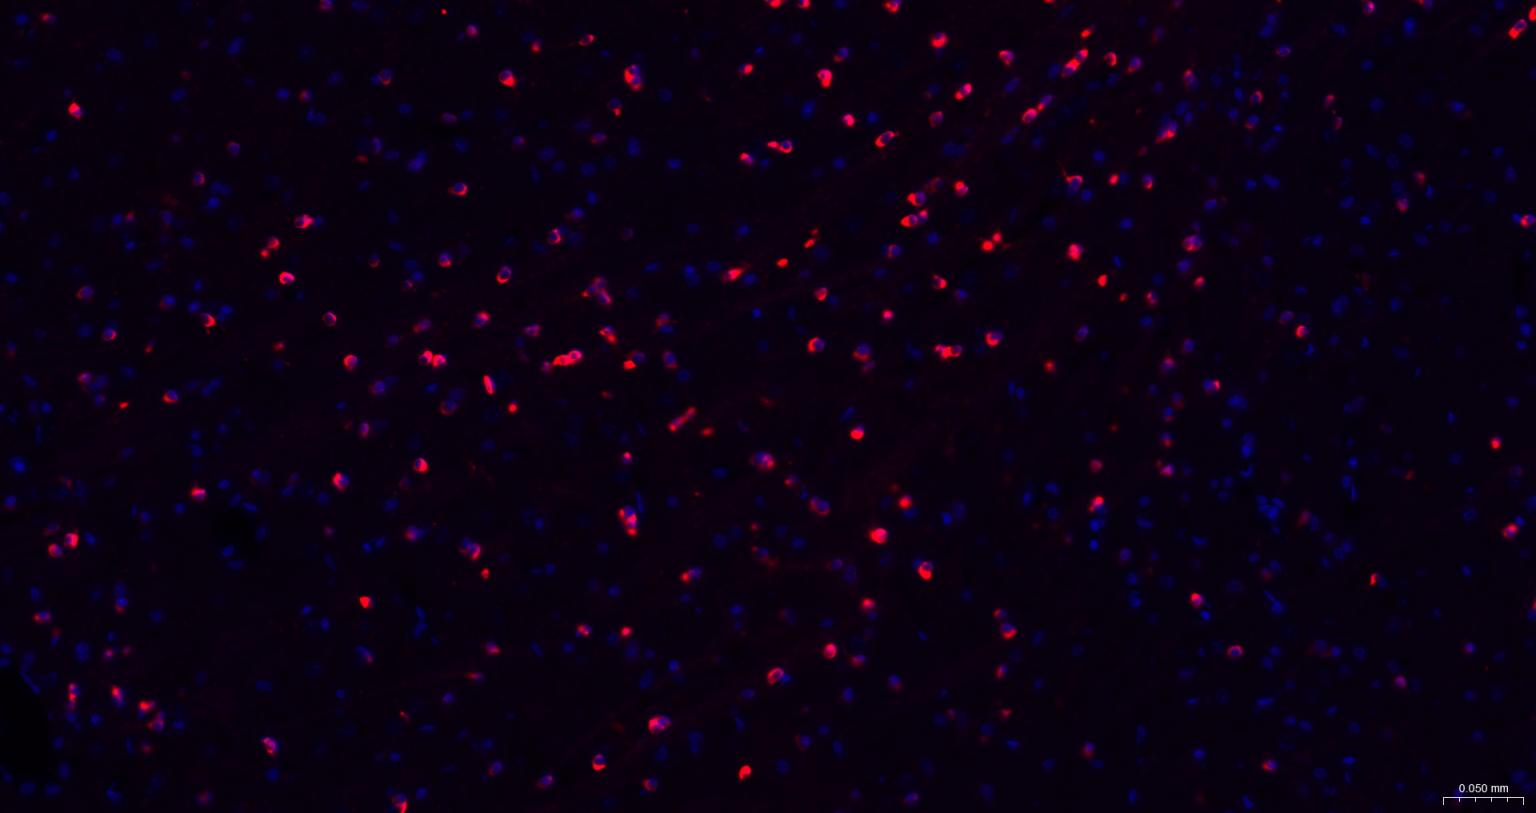

Paraformaldehyde-fixed, paraffin embedded Human Left parietal lobe; Antigen retrieval by boiling in sodium citrate buffer (pH6.0) for 15 min; The section was incubated with NMDAR1 Monoclonal Antibody, Unconjugated (bsm-52950R) at 1:200 overnight at 4°C. Followed by conjugated Goat Anti-Rabbit IgG antibody (Red, bs-0295G-BF594), DAPI (blue, C02-04002) was used to stain the cell nuclei.